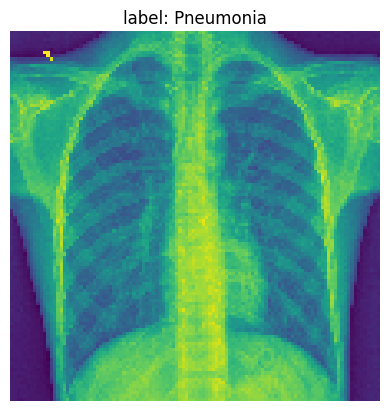

We are going to pick one example from our test data to visualize some of the our MLP model activations after each layer. Below we print the original image.

img_idx= 14

test_img_tensor = x_test_t[img_idx].unsqueeze(0).cpu()

plt.imshow(test_img_tensor[0]);

plt.title(f'label: {full_label(str(y_test_t[img_idx]))}')

plt.axis('off')

plt.show()